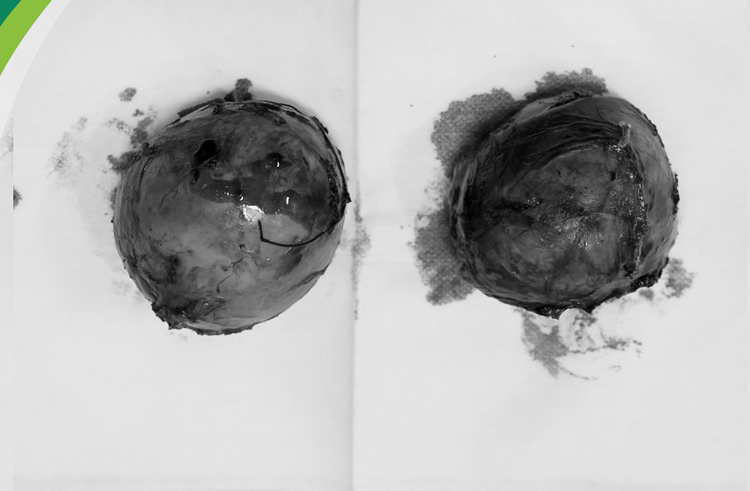

![]() |

| 2 khối u tuyến thượng thận được lấy ra |